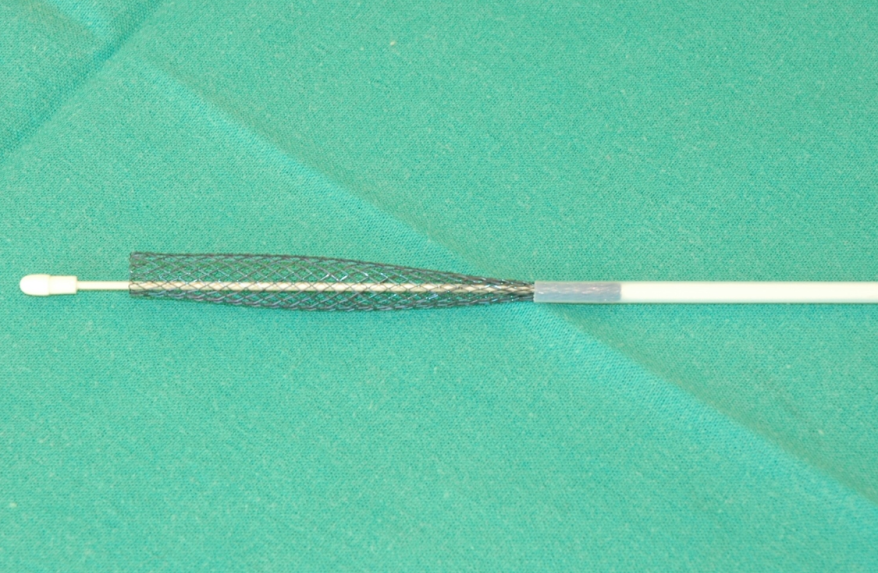

На сегодняшний день лучшие результаты получены при стентировании внутреннего просвета трахеи сеточными конструкциями, которые поддерживают просвет трахеи и способны выдерживать нагрузки, характерные для данной анатомической области.

В нашей клинике мы применяем нитиноловые стенты американской фирмы DEXTRONIX. ЭТО СПЕЦИАЛЬНО РАЗРАБОТАННЫЕ КОНСТРУКЦИИ ДЛЯ ИСПОЛЬЗОВАНИЯ У СОБАК И КОШЕК, изготовленные из сплава никеля и титана. Эти металлы не раздражают биологические ткани, одновременно являясь прочными и гибкими. Таким образом, они способны выдерживать большие нагрузки и при этом не вызывают воспалительных реакций со стороны организма. Оригинальное плетение изготовлено так, что составляющие сетку нити плетутся концами внутрь стента в направлении к центру, поэтому конец конструкции не раздражает и не травмирует прилегающую трахею.

DEXTRONIX- нитиноловые эндотрахеальные стенты